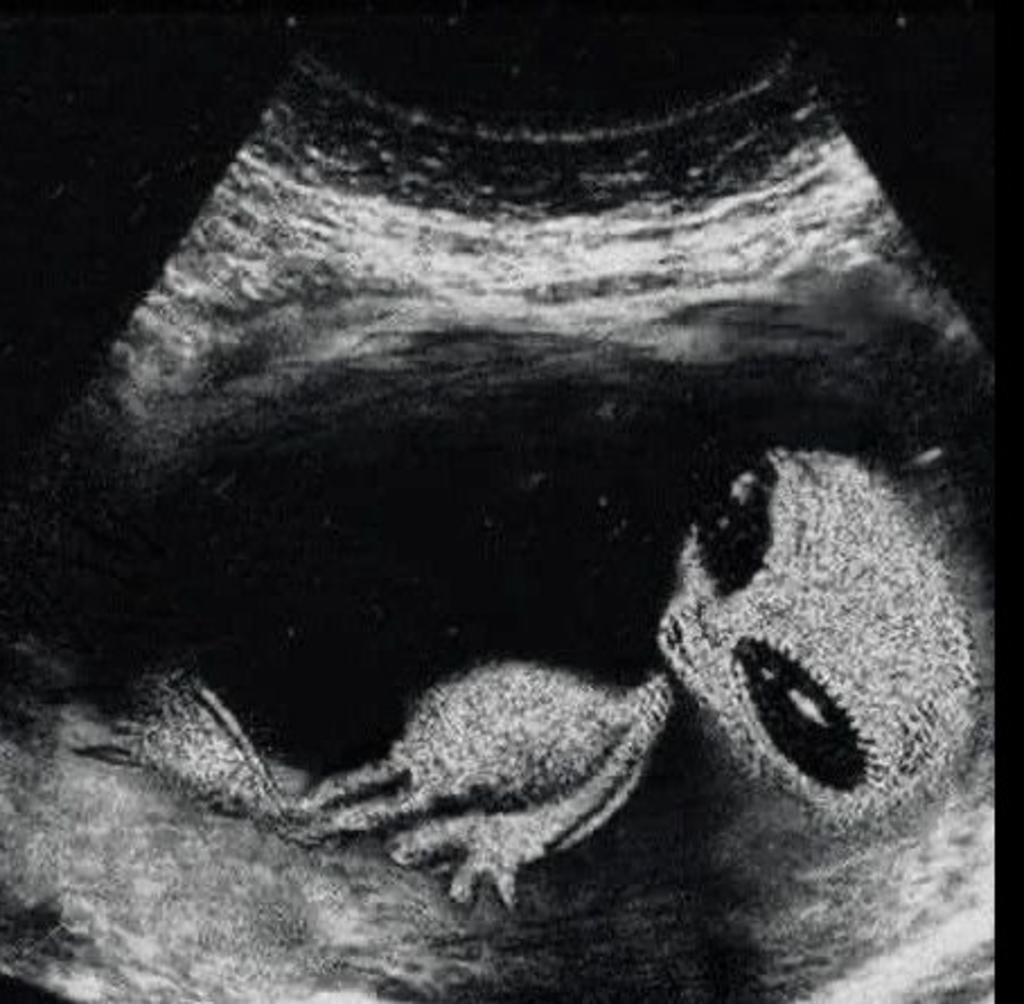

hand: con t bị sao thế này

n/l:con bị j vậy con,ôi con tôi.